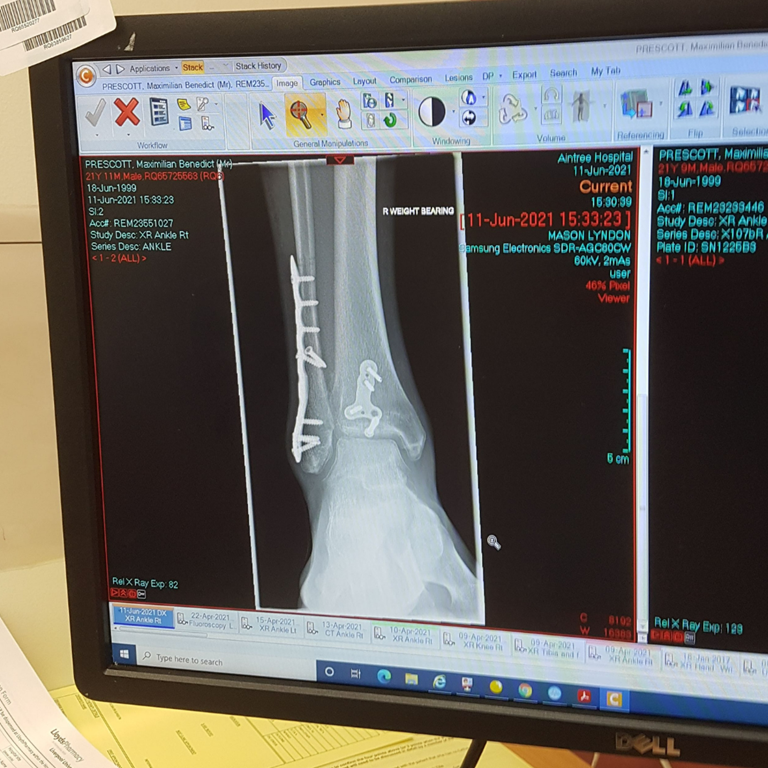

I broke two bones in my ankle and ruptured my deltoid ligament, meaning it was an unstable ankle fracture and would require surgery (see Picture 2). I was told it would be a good outcome if I could walk again without pain. The first two weeks were all about managing pain, resting, and keeping the ankle elevated to reduce the swelling for the surgery. After the surgery, the following two weeks were much of the same until the cast could be removed. Essentially, I would spend the whole day in bed only getting up to make food or go to the bathroom.

I was told by the doctors that I might not be able to walk again without pain, which is a possibility I had to come to terms with. However, I knew that I would do everything in my power to ensure the best possible recovery. Four days after the surgery, I began to do what exercise I could. I did my first set of pullups since the accident (I thought my heart was going to beat out of my chest from being so unfit!), and I started doing daily grip strengthening exercises and core workouts. As my confidence grew, I began to do more rigorous workouts, and two weeks after the operation, they removed the cast and stitches.

However, at times, I pushed my ankle too far. I remember one particularly strenuous climbing session in October where afterwards my ankle felt a lot more tender, and a dimple appeared over the plate. I went to get it checked out and it was likely one of the screw heads rubbing against the skin. I had to take it easy for the next couple weeks.

Jump forward a few months and I am now climbing stronger than ever before. I’ve started projecting my hardest ever climb outdoors and have managed it in two halves! However, the plates continued to cause me irritation and so I have just had an operation to have them removed. That felt like the next step in my personal journey towards a full recovery (not everyone has them removed).